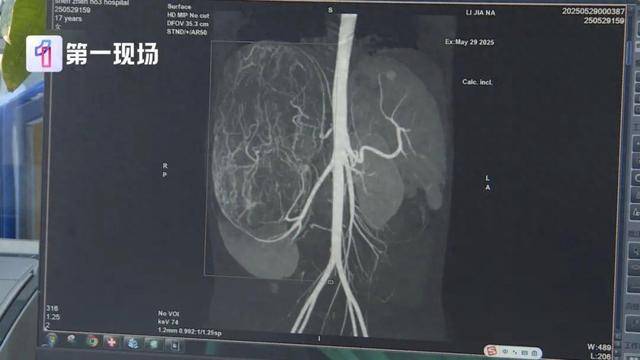

广东17岁女孩婷婷(化名) 今年还在读高二 前段时间 妈妈带着她去逛街买衣服 试裤子的时候店员来帮忙 感觉孩子身形消瘦 但是肚子却有点大 于是建议妈妈带她去医院看看 结果,不查不知道,一查吓一跳 婷婷